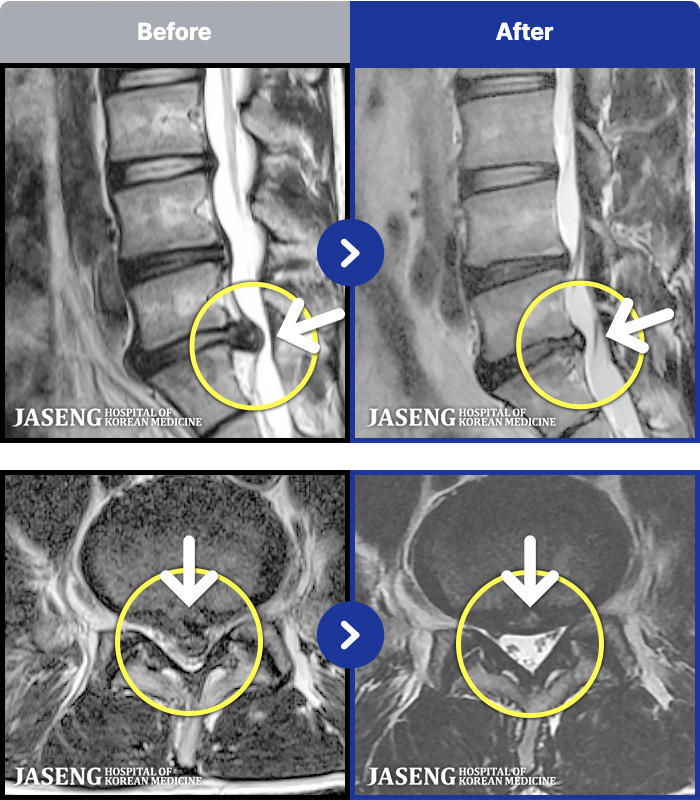

MRI ġ

1,304 MRI ũ ʸ Ȯϼ.